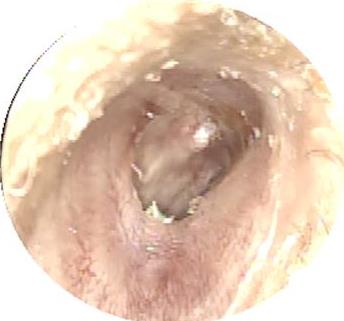

摘要:目的 分析医用生物蛋白胶应用于耳内镜下鼓膜修补术的临床疗效。方法 回顾性分析2022年10月-2023年10月该院收治的60例单纯鼓膜穿孔患者的临床资料,根据手术方法不同,将患者分为研究组和对照组,各30例。研究组术中使用医用生物蛋白胶粘合残余鼓膜和修补材料;对照组术中采用明胶海绵覆盖修补鼓膜。观察两组患者术后的鼓膜愈合情况(鼓膜愈合率、愈合时间、干耳时间和外耳道上下径)和并发症发生情况;于手术前后,采用纯音测听法(500、1 000、2 000、4 000 Hz),测量两组患者气导阈值,观察听力改善程度;采用视觉模拟评分法(VAS)评分,评估患者术后疼痛程度。结果 两组患者术后鼓膜愈合率、愈合时间、外耳道上下径和并发症发生率比较,差异均无统计学意义(P > 0.05)。研究组术后平均气导听阈明显低于对照组,差异有统计学意义(P < 0.05)。研究组术后干耳时间短于对照组,术后第1天疼痛VAS评分明显低于对照组,差异均有统计学意义(P < 0.05)。结论 医用生物蛋白胶应用于耳内镜下鼓膜修补术,可有效地降低气导听阈,缩短干耳时间,减轻患者疼痛,且不增加并发症发生率,值得临床推广应用。